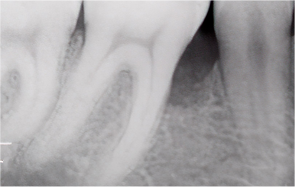

Even when severe periodontal disease has caused gingival recession and alveolar bone resorption, teeth can often be preserved through gum regeneration therapy using Emdogain. This procedure regenerates damaged alveolar bone and surrounding periodontal tissue. By applying Emdogain — a specialized gel that stimulates periodontal tissue regeneration — the supporting structures of the tooth are rebuilt, allowing function and health to be restored without extraction.

Supports regeneration of alveolar bone damaged by chronic periodontitis

Restores periodontal tissue, alveolar bone, and periodontal ligament around teeth

Before & After